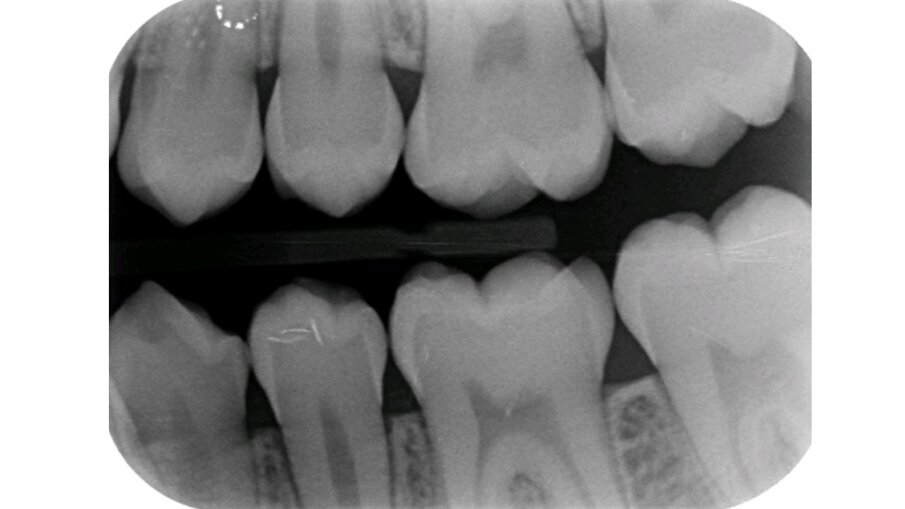

Het eerste kind waarbij wij NRC toepasten was 6 jaar. Op de bitewings werden cariëslaesies bij alle vlakken van de aangrenzende melkmolaren gediagnosticeerd. Met de ouders werd besproken wat onze plannen waren. Zij gingen hiermee akkoord. In de volgende zitting werden de 8 vlakken beslepen (afbeelding 1a-b). De behandeling verliep probleemloos en werd goed geaccepteerd. Maar in het vervolgtraject hebben we steken laten vallen. De voorlichtende communicatie gebeurde hoofdzakelijk traditioneel. De terugkomtermijn besloeg een paar keer achter elkaar een interval van bijna een jaar. Daar verander je geen gedrag mee. De verslaggeving ontbrak een aantal keren. Bijna 6 jaar later werd geconstateerd dat er veel plaque aanwezig was. De wisseling had inmiddels plaatsgevonden. Restauratief of chirurgisch ingrijpen is sinds NRC werd toegepast niet nodig geweest en de bitewings vertonen geen cariësactiviteit (afbeelding 2a-b). Ook waren geen sealants noodzakelijk geweest.

Afbeelding 2a. Bitewings van de blijvende dentitie.

Afbeelding 2b. Bitewings van de blijvende dentitie.